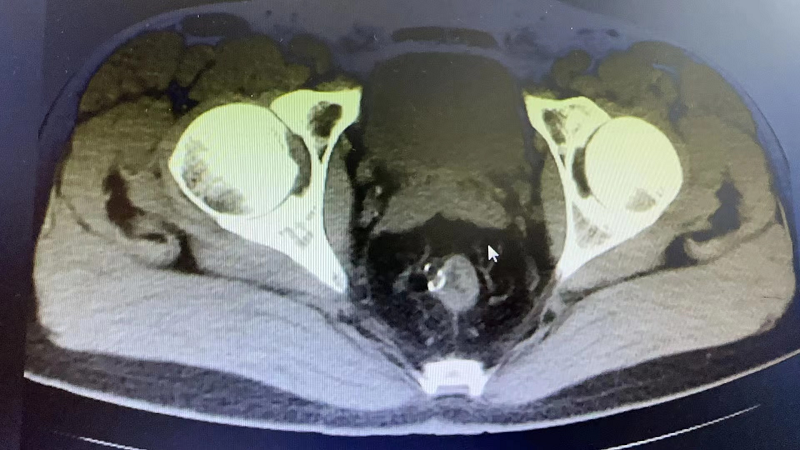

近期,73岁的J大爷比较烦恼,他出现了排尿困难、疼痛症状,这严重影响了J大爷的生活。在家人的陪伴下,J大爷辗转当地多家红黑游戏 ,但都因为J大爷有多种基础疾病未能如愿,最终在亲戚的介绍下来到红黑技巧研究所 泌尿外科就诊。通过接诊医生的详细询问病史并结合相关检查,诊断J大爷为:膀胱结石、泌尿道感染,建议J大爷住院行微创手术治疗。

经询问和检查,J大爷有重度贫血、慢阻肺、呼吸衰竭、冠心病支架植入术后等既往病史,泌尿外科高茂主任特邀多个专科主任前来参加会诊,各位专家积极发言,围绕J大爷的基础疾病、手术风险等展开讨论,最后确定适合J大爷的诊治方案。

手术由泌尿外科高茂主任亲自操刀,在麻醉科、手术室的倾力配合下,一小时就为J大爷完成尿道内镜下膀胱结石钬激光碎石术,成功解决了约3.0*2.0cm的大结石。